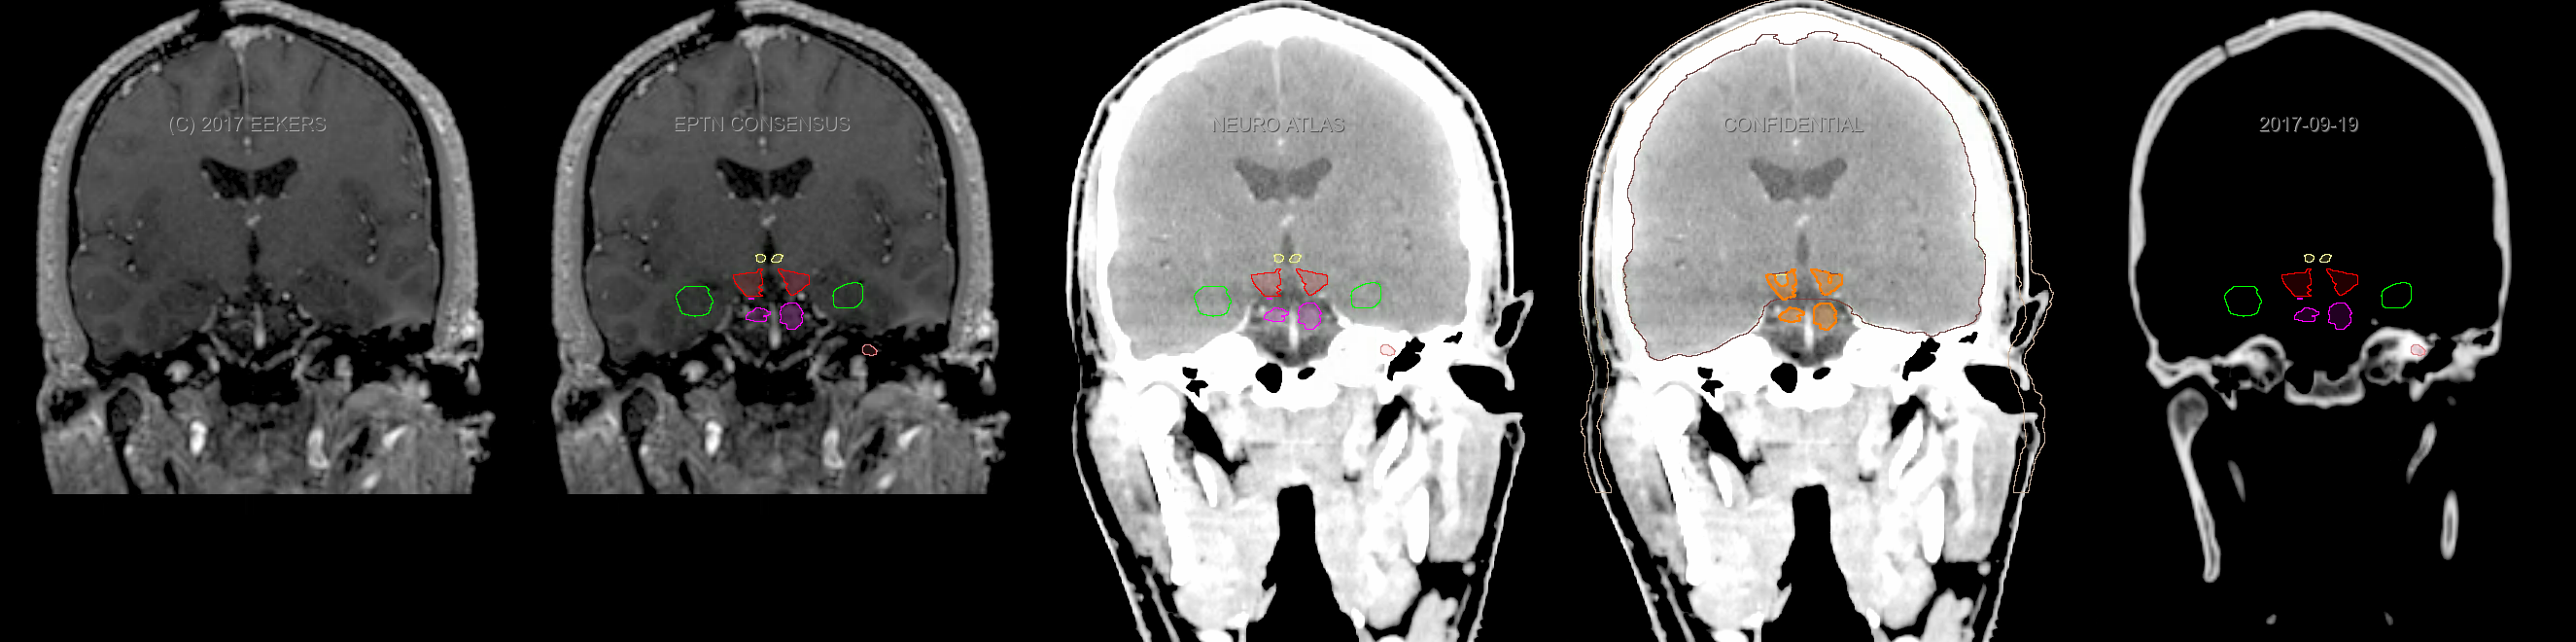

Three-dimensional delineation of the fifteen consensus OARs for neuro-oncology are shown on CT and 3 Tesla (3T) MR images (slice thickness 1 mm with intravenous contrast agent). All are presented in transversal, sagittal and coronal view.

From left to right: MR without structures, MR with structures, CT (WW/WL 120/40) with structures, CT (WW/WL 120/40) with Brain and Brainstem Surface, CT (WW/WL 1500/120)with structures